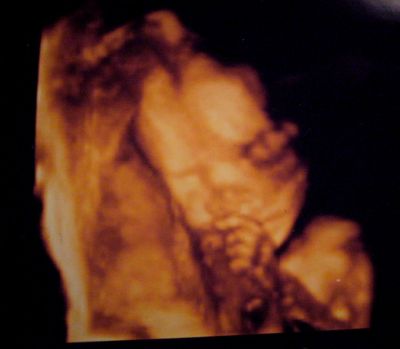

Akkor a 20 hetes pocakok.

19+5

20+0